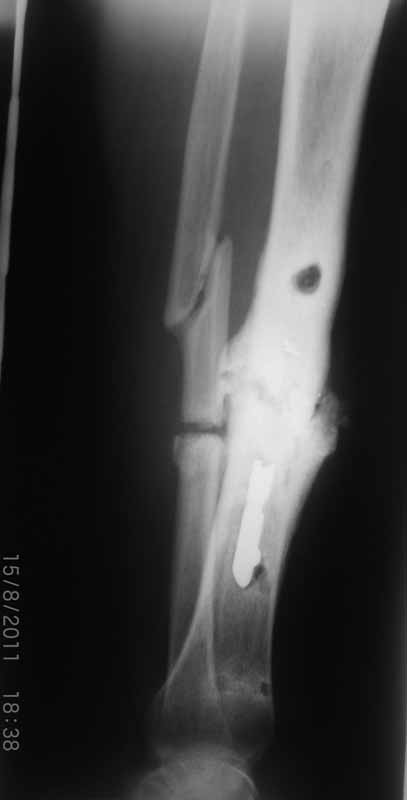

Примерная ситуация. Пациент 37 лет. Синтезировали где-то пластинкой. Попал к нам через 2 месяца.

19 апреля убрали через проколы пластину с винтами, пересекли fibula, наложили аппарат.

Немного потянули по оси, убрали вальгус, ротацию. 22 апреля (на 3-е сутки) заштифтовали окончательно. 29 апреля выписали из отделения. На все ушло 10 дней.

С уважением, Никита Заднепровский